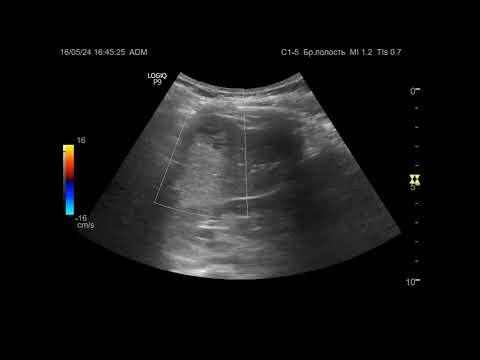

Ультразвуковая диагностика. Доктор Иогансен. Видеопримеры. Выпуск 108. Панкреатолитиаз (2).